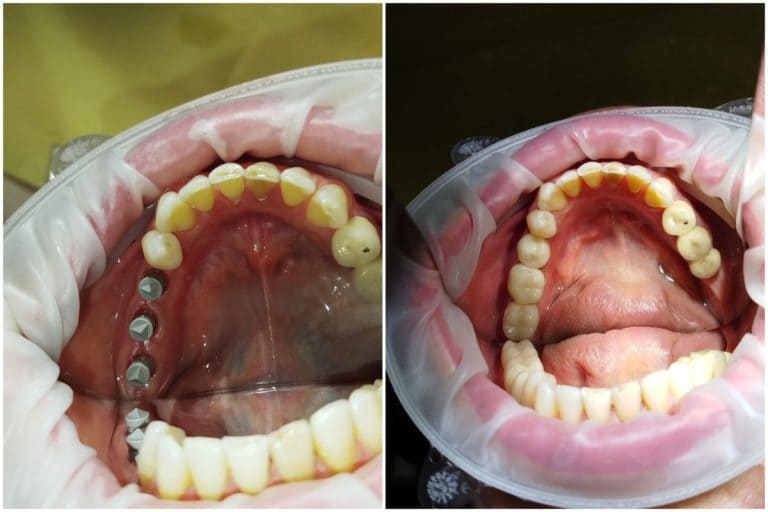

Одномоментная имплантация

Цель визита пациента

- Причина обращения в нащу клинику - перелом коронки зуба

Детали лечебного процесса

- Пациенту было рекомендовано удаление корня 45 зуба с одномоментной установкой имплантата в области 45 зуба. В рамках одного визита также выполнено лечение 46 зуба с фиксацией керамической коронки.

Продолжительность и этапы лечения

- 1 день

- 1 визит